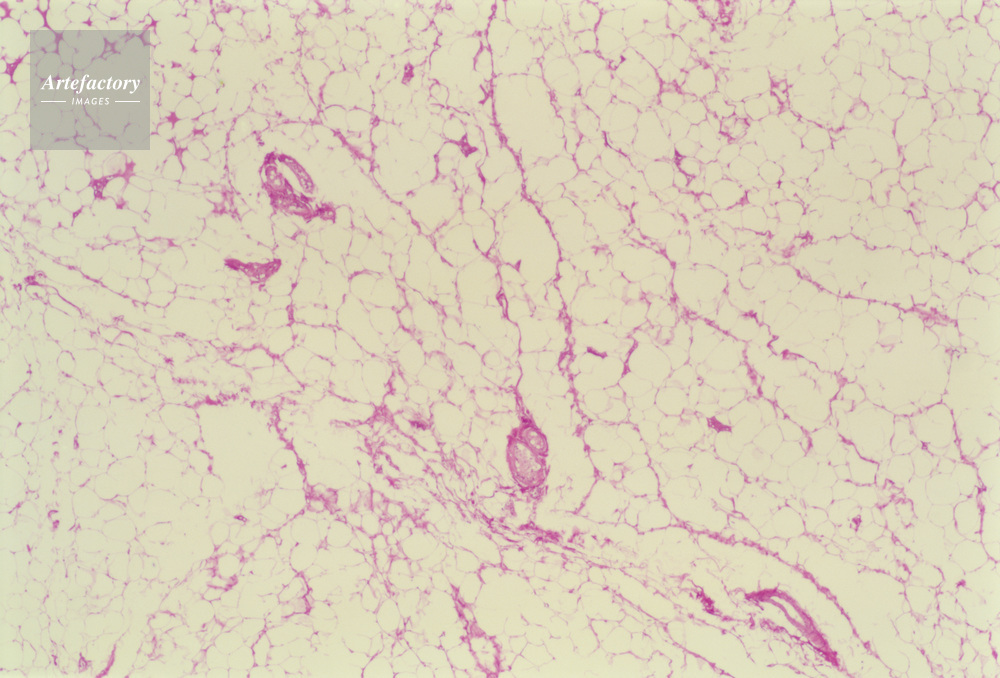

| キャプション | 脂肪組織,人間,20倍 | 制限事項 | ||

| ソース | ピクセル数 | 5561px × 3769px | ||